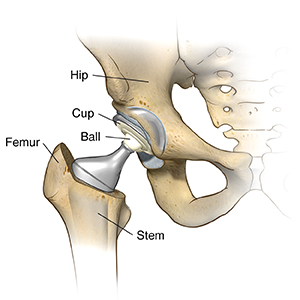

The surgeon will remove the damaged parts of the hip joint and replace them with the prosthesis. The hip prosthesis is made up of a stem that goes into the thighbone (femur), the head joint (ball) that fits into the stem, and a cup that is inserted into the socket of the hip joint. The stem and cup are made of metal. The ball may be made of metal or ceramic. The cup has a liner that may be made of plastic or ceramic. The two most common types of artificial hip prostheses used are cemented prostheses and uncemented prostheses. A cemented prosthesis attaches to the bone with surgical cement. An uncemented prosthesis attaches to the bone with a porous surface. The bone grows onto this surface to attach to the prosthesis. Sometimes a combination of the two types is used to replace a hip.